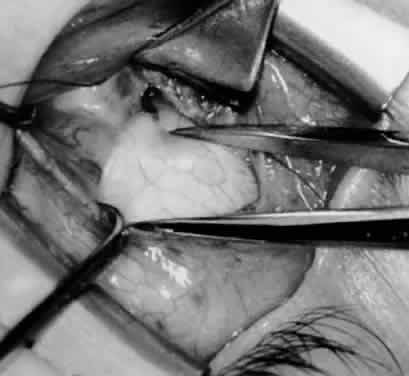

Fig. 21. A hemostat is placed adjacent to the insertion of the right inferior oblique muscle.

Fig. 22. An Aebli scissor is used to section the inferior oblique muscle from the globe.

Fig. 23. The inferior oblique muscle is drawn into the operative field with a hemostat. This step may be used for the recession procedure if the surgeon is concerned about the placement of the 6-0 Vicryl suture while the muscle is attached to the globe in the proximity of the macula. The recession sequence would follow after the placement of the suture while the muscle is grasped in the hemostat.